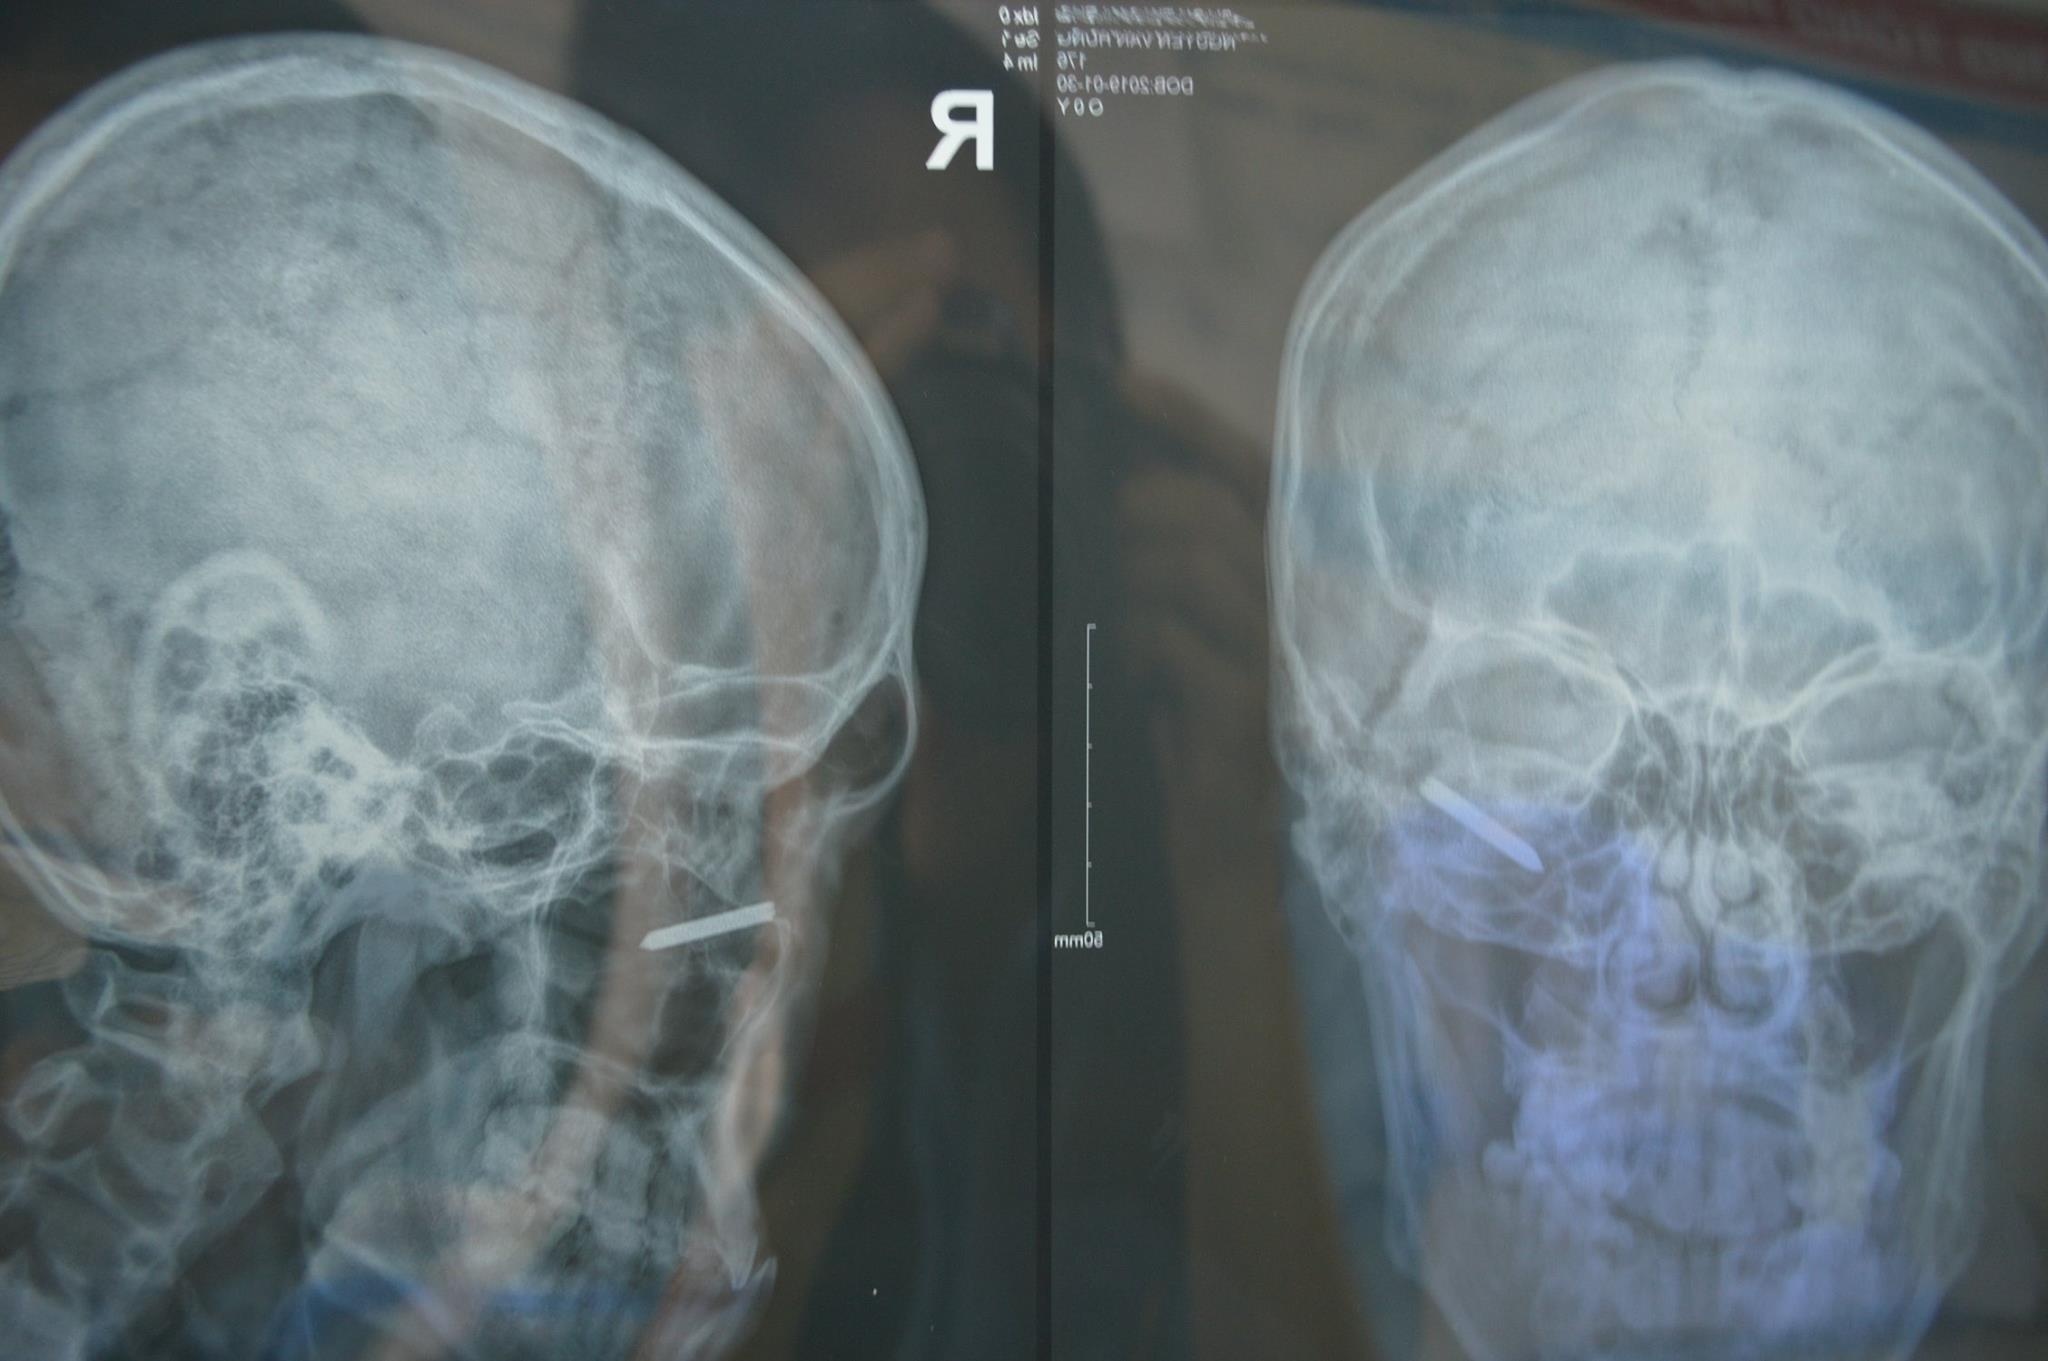

| Hình ảnh chụp X-quang cho thấy một phần cây đinh dài 3 cm cắm sâu trong hốc mắt bệnh nhân. Ảnh: BVCC. |

Quan sát trên phim chụp, vết thương nhìn thấy chỉ là một vùng rách da nhỏ ở mi dưới ngoài nơi cây đinh xuyên qua, rất khó xác định đầu đinh vì đã cắm khá sâu, có nguy cơ tụt vào xoang hàm nếu có tác động.